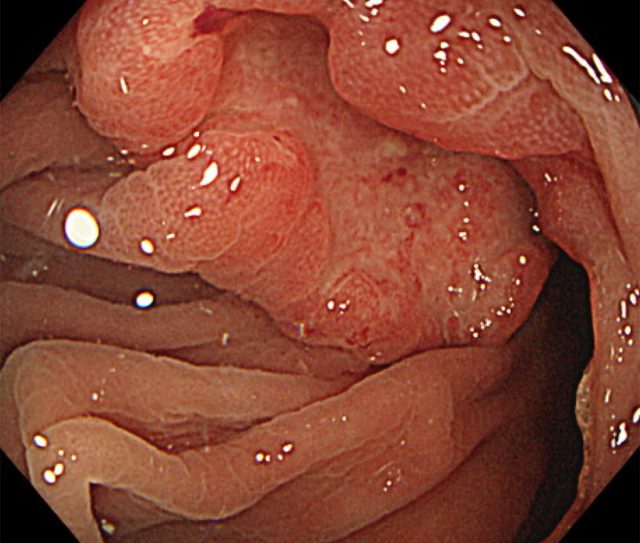

大腸ポリープ・大腸がん

大腸がんは、大腸(結腸・直腸)にできるがんで、日本では罹患数が非常に多いがんです。

早期では自覚症状がないことが多く、進行すると血便、便秘や下痢などの便通異常、腹痛、腹部膨満感、貧血などが現れます。

早期の段階で発見し治療すれば完治する可能性が高く、特に40歳以上になったら大腸がん検診を受けることが推奨されます。

大腸にできるポリープは、大きく「腫瘍性ポリープ」と「非腫瘍性ポリープ」に分けられます。

一部例外はありますが、問題となるのは腺腫に代表されるような腫瘍性ポリープです。腺腫は時間とともに大きくなり、やがて“がん化”していく前癌病変と考えられ、基本はすべて切除するべきとされています。